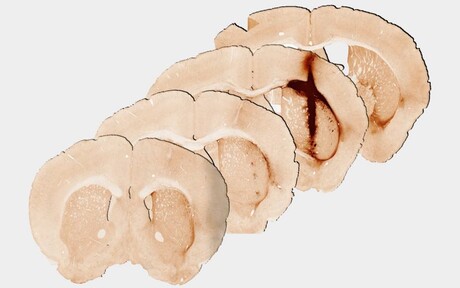

Melbourne’s Professor Clare Parish conducted the mouse studies and said promising results were achieved in injured brain tissue, raising the possibility for growing new tissue for future human treatment. “Analysis at 28 days after delivery of the hydrogel revealed significantly enhanced survival and growth of the new stem cells that are needed for healthy brain functioning, compared with a hydrogel without myoglobin,” Parish said.

“We observed that the new tissue could be stimulated in a similar way to healthy brain tissue, providing the first evidence of the benefits of including oxygen delivery within a hydrogel to achieve the long-term survival and integration of stem cell transplants.”